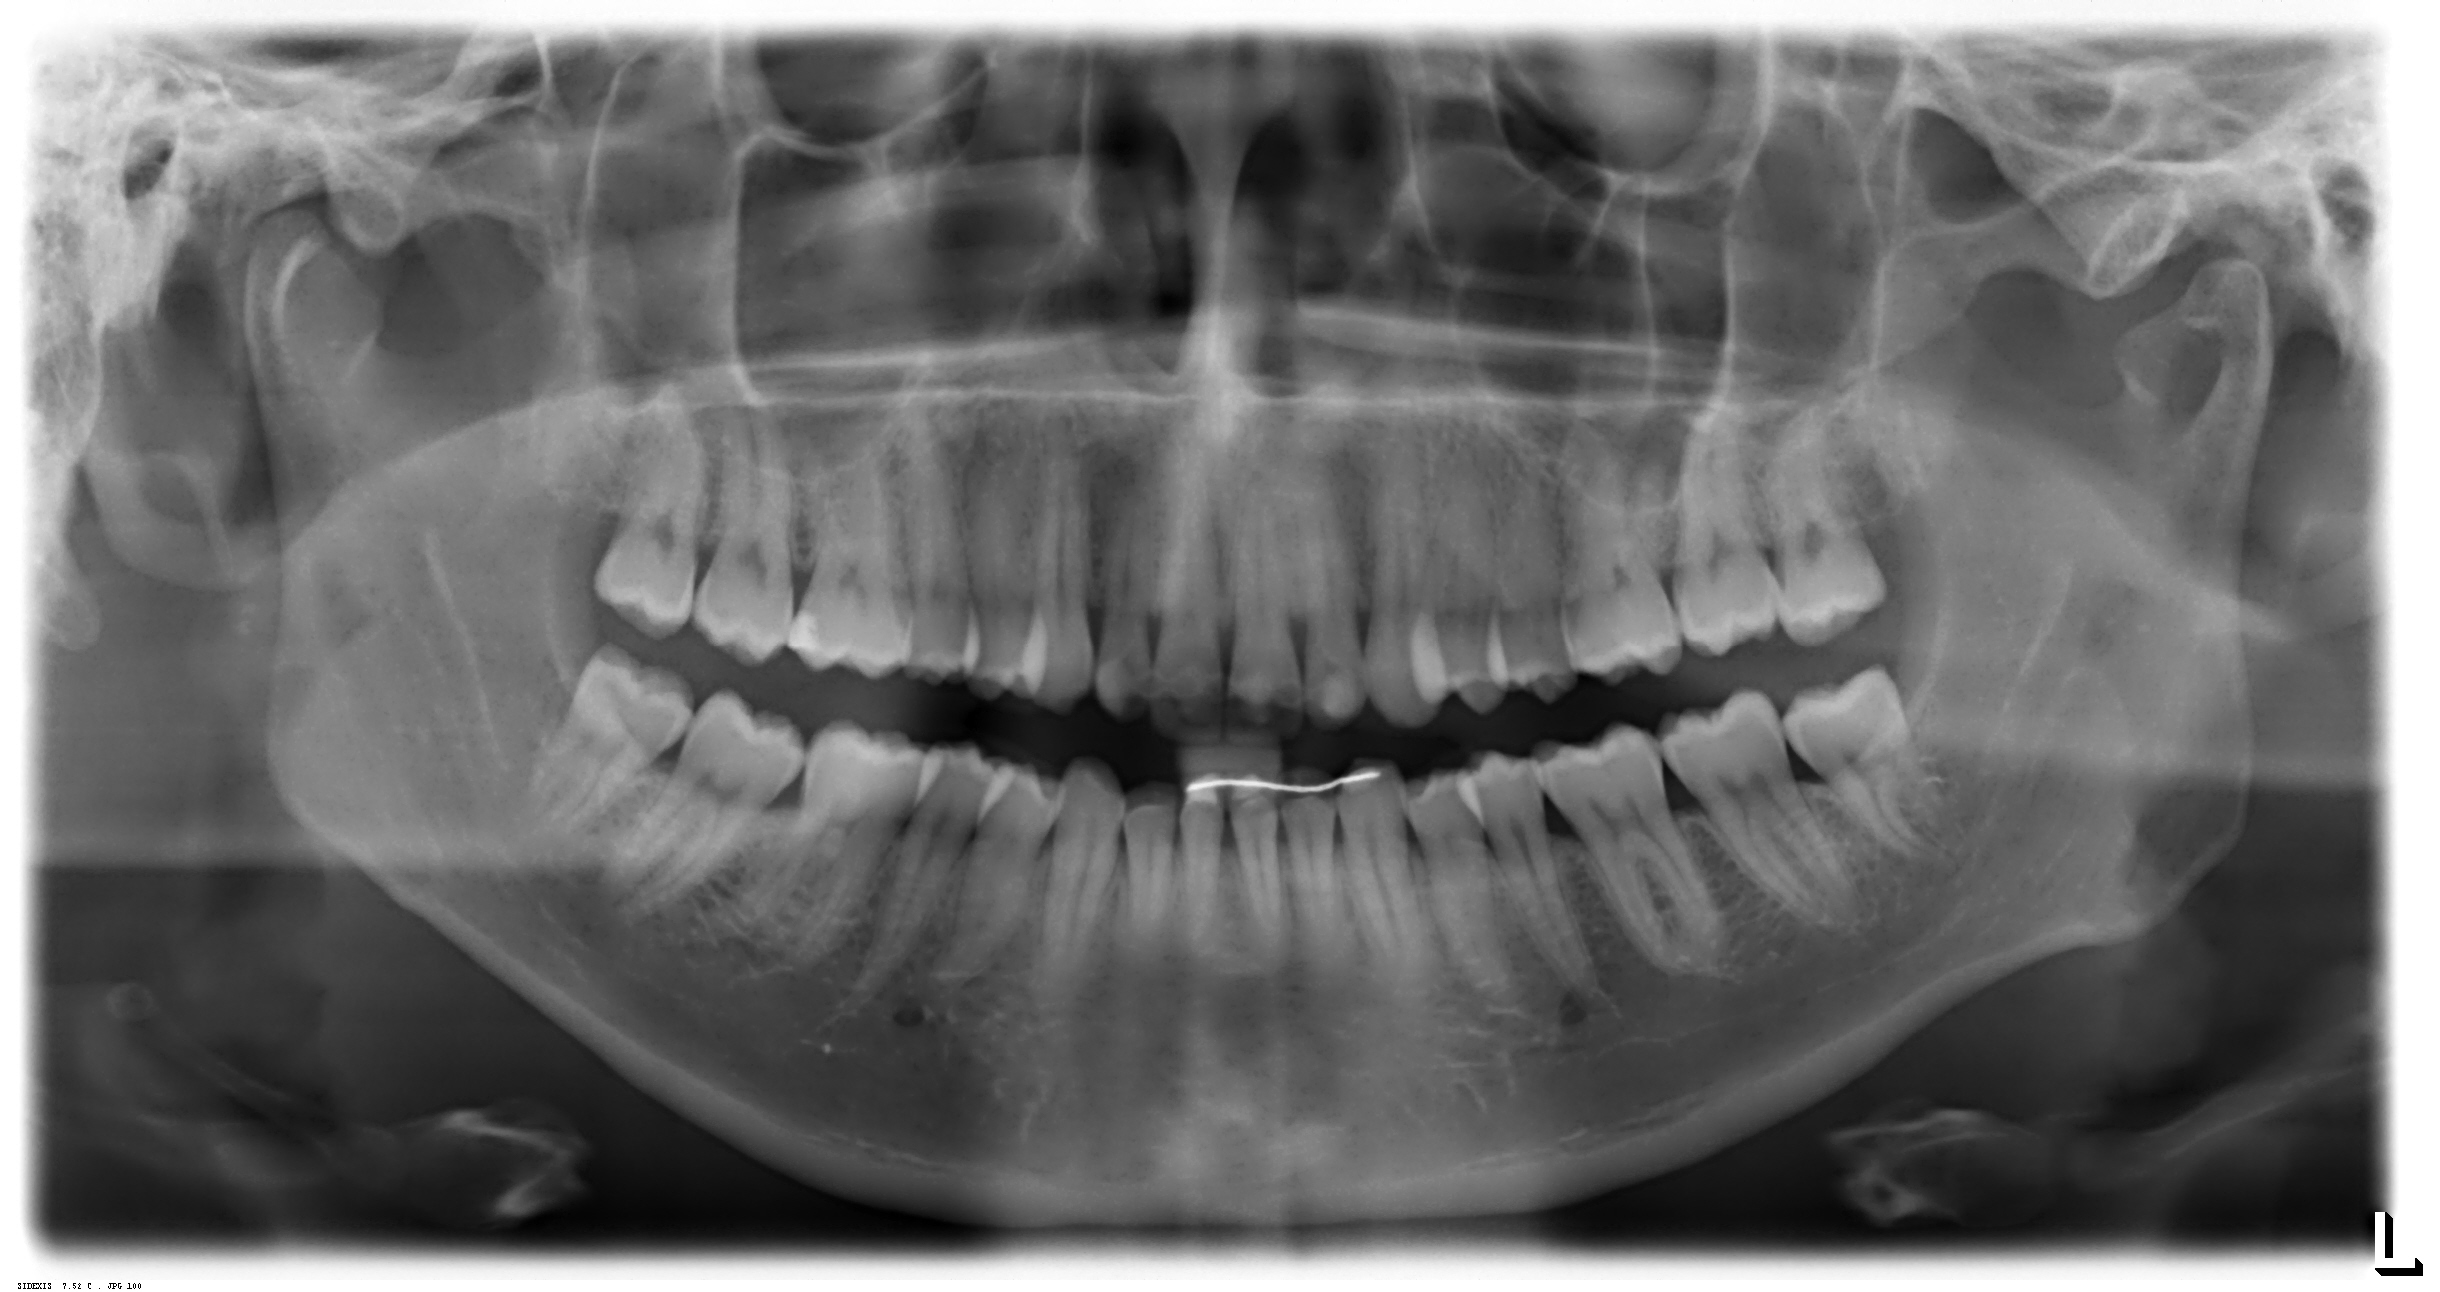

Im November des vergangenen Jahres erlitt ich beim Eislaufen einen Unfall und fiel auf die oberen Frontzähne, die jedoch beide intakt blieben. Von November bis März war ich bei mehreren Kontrollen inklusive Röntgen in der Zahnuniversitätsklinik, außerdem wurde bei jedem Kontrollbesuch ein Kältetest durchgeführt, bei dem ich beide Zähne mit Verzögerung spüren konnte.

Erst beim letzten Kontrollbesuch am 11.03 konnte im Kleinbildröntgen ein geringgradiger Schatten / eine Entzündung festgestellt werden (siehe Bilder), woraufhin mir eine Wurzelbehandlung empfohlen wurde.

28.11.2019:

23.01.2020:

20.02.2020

11.03.2020

wirkt röntgenologisch “normal” – zudem wenn der kälte test positiv ist, wieso wb?